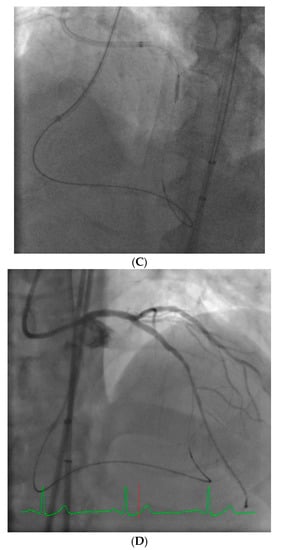

Figure 4.

This is an example of a poor choice for robotic PCI. The patient has a single coronary artery with an ejection fraction of 20% and the lesion is very complex in the artery with severe tortuosity and angulation.

Figure 6.

Ostial RCA lesions can be very challenging to perform robotically due to the complex interactions between the guide catheter position and stent catheter.